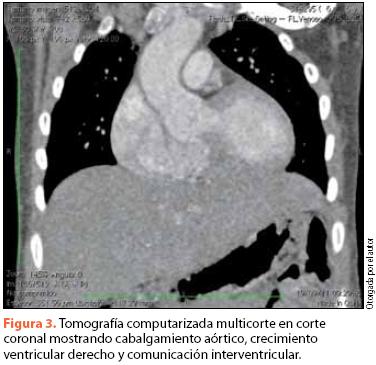

Se procedió a realizar un ecocardiograma, en el que se encontró hipoplasia del anillo pulmonar, estenosis pulmonar mixta de predominio valvular, comunicación interventricular subarterial de 6.7 x 8.8 mm, ventrículo derecho hipertrófico, rama derecha de la arteria pulmonar hipoplásica, cabalgamiento aórtico del 40% y FEVI de 73% (figura 2). Se realizó también tomografia computada, en la cual se corroboró la estenosis pulmonar y se observó dilatación de la aorta ascendente, persistencia de vena cava superior izquierda y disminución en el diámetro de la rama pulmonar derecha (figura 3).

El cateterismo permite determinar la importancia de las alteraciones hemodinámicas y la presencia de salto oximétrico al pasar de la aurícula derecha al ventrículo derecho si las presiones derechas no han vencido aún las izquierdas18. El uso de la tomografía computada y la resonancia magnética, a pesar de no aportar datos adicionales en cuanto a la morfología cardiaca respecta, pueden ser útiles para descubrir la presencia de alteraciones morfológicas o funcionales en general, ilustrado en nuestro caso por la confirmación de la hipoplasia de la arteria pulmonar derecha y el descubrimiento de una vena cava supernumeraria19,20.